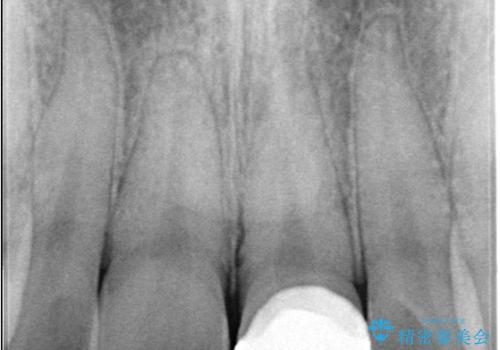

神経の状態が良好に保たれていることを確認した後、オールセラミッククラウンによる審美修復を行いました。

他院では「治療が難しい」と言われた患者様でしたが、当院で神経を残すことができ、見た目もきれいに仕上がったことで大変喜んでいただけました。